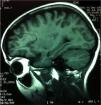

La analítica de sangre mostró: hemoglobina: 11,5g/dL; leucocitos: 5.200/μl; plaquetas: 143.000/μl; creatinina: 0,76mg/dL; urea 40mg/dL, Velocidad de sedimentación globular (VSG): 14mm/h; factor reumatoide: 1mg/L; anticuerpos antinucleares negativo, anti-ADN negativo; complemento total: 800 U/mL, C3: 67mg/dL (90-180); C4: 6,21mg/dL (10-40); C5: 57,1mg/dL (15-30); anticuerpos anticardiolipina IgG: 107 GPL/mL (0-20); anticardiolipina IgM: 38 MPL/mL (0-18); anticoagulante lúpico: 40,4 (34-40,4); anti-β2-glucoproteína IgG: 95 U/mL (< 7); anti-β2-glucoproteína IgM: 19 U/mL (7-10); anticuerpos anticitoplasma de neutrófilos negativo; antimembrana basal glomerular IgG negativo. La coagulación fue normal. El líquido cefalorraquídeo mostró una celularidad de 2/mm3; proteínas: 19,1mg/dL, y glucosa 51mg/dL. La proteína C reactiva (PCR) a virus neurotropos fue negativa. Las bandas oligoclonales, niveles de IgG, anticuerpos anti-N-metil D-aspartato (NMDA-R) y antiganglios basales en el LCR fueron negativos. La biopsia renal mostró datos de glomeruloesclerosis segmentaria y focal, con infiltrado linfocitario focal de menos del 50% de los glomérulos, positividad segmentaria con IgM y mesangial de C3; IgA e IgG negativas. La resonancia magnética craneal mostró imágenes milimétricas con captación de contraste en la sustancia blanca subcortical y en la convexidad de hemisferios cerebrales, indicativas de microlesiones (fig. 1).